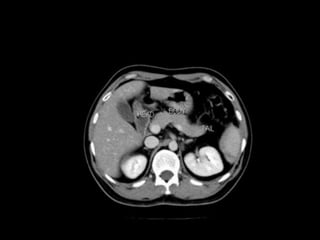

Cross section anatomy of abdominal ct scan

Cross section anatomyof abdominal ct scan